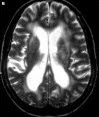

T2-weighted images cause wáter ( eg,CSF and edema) to appear

bright and fat to appear dark.